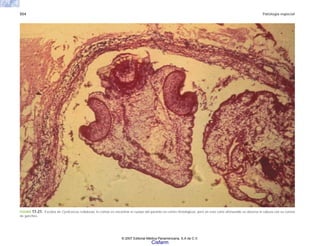

104 Patología general

FIGURA 6-23. Criptococo teñido con azul alciano que muestra las estructuras esféricas y la cápsula con material mucoide.